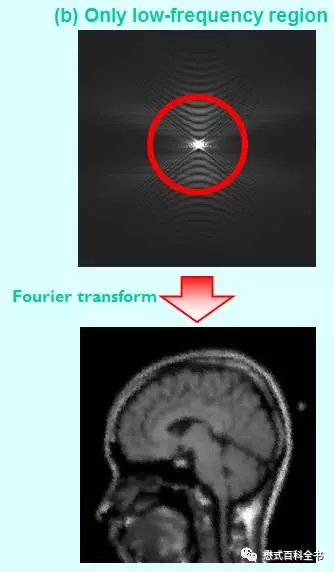

图14:只利用K空间中心部分数据来做图像重建,把周围数据丢弃掉。可以发现重建出来的图像,对比度比较好(基本上跟图13差不多),但是空间分辨率不够,解剖细节模糊。